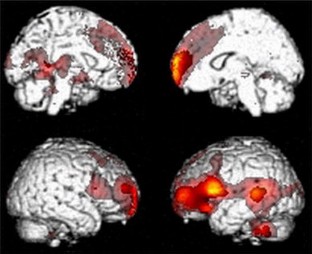

We observed a metabolic impairment in a bilateral subcortical (thalamus and caudate) and cortical (fronto-temporo-parietal) network in nontraumatic and traumatic MCS patients. Compared to MCS−, patients in MCS+ showed higher cerebral metabolism in left-sided cortical areas encompassing the language network, premotor, presupplementary motor, and sensorimotor cortices. A functional connectivity study showed that Broca’s region was disconnected from the rest of the language network, mesiofrontal and cerebellar areas in MCS− as compared to MCS+ patients.

The proposed subcategorization of MCS based on the presence or absence of command following showed a different functional neuroanatomy. MCS− is characterized by preserved right hemispheric cortical metabolism interpreted as evidence of residual sensory consciousness. MCS+ patients showed preserved metabolism and functional connectivity in language networks arguably reflecting some additional higher order or extended consciousness albeit devoid of clinical verbal or nonverbal expression.